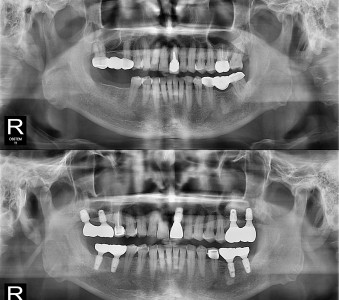

결과로 증명합니다.

국제모아치과의

실제 임상 증례